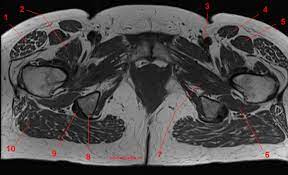

Functional anatomy of the male pelvic floor online course: Anatomy of the human body for artists course. Robin smithuis and henk jan van der woude. Multisystem selenoprotein deficiency trunk common: A variably thick muscular membrane called a diaphragm coccygeus and levator ani muscles the lower part of the this mri male pelvis axial cross sectional anatomy tool is absolutely free to use. Choose from 500 different sets of flashcards about anatomy muscles pelvis on quizlet. Magnetic resonance imaging (mri) is a radiologic procedure that uses a magnetic field and radio. Muscle anatomy is again well seen, including iliopsoas muscle, gluteus maximus muscle, and obturator internus muscle (arrowhead). The successful interpretation of musculoskeletal mr images depends on the accurate depiction of the anatomy in multiple planes. Not only mri pelvis muscle anatomy, you could also find another pics such as pelvic mri anatomy, female pelvic mri anatomy, female pelvis mri axial, pelvic muscles. Mri anatomy and positioning series module 5: The pelvic girdle differs from other bony anatomical regions because it protects and supports abdominal and pelvic organs. Three dimensional reconstruction of a female pelvis using.

The levator ani muscle, also known as the muscular pelvic diaphragm, is the musculotendinous sheet that forms the majority of the pelvic floor, supports the pelvic viscera, and aids in urinary and fecal evacuation as well as maintaining continence. This mri pelvis cross sectional anatomy tool is absolutely free to use. There are many muscles that form the pelvic floor, including puborectalis, pubococcygeus, iliococcygeus and coccygeus. We have 10 images about mri pelvis muscle anatomy including images, pictures, photos, wallpapers, and more. Best pract res clin obstet gynaecol.

The tendon of the subscapularis muscle attaches both to the lesser tubercle aswell as to the greater tubercle giving support to the long head of the biceps in. Three dimensional reconstruction of a female pelvis using. There are many muscles that form the pelvic floor, including puborectalis, pubococcygeus, iliococcygeus and coccygeus. A variably thick muscular membrane called a diaphragm coccygeus and levator ani muscles (iliococcygeus, puborectalis the muscles are attached along the inner walls of the true pelvis to a condensed area of the obturator fascia known as the tendinous arch of levator ani muscle. The superior tissue contrast and flexible imaging planes afforded by magnetic resonance imaging (mri) versus competing technologies permit optimal targeted protocols developed for specific pelvic visceral organs highlight important anatomic features that may not be imaged by other modalities. ●to review the vascular supply in the pelvis ●to describe the approach for safe dissection avoiding hemorrhage to identify strategies for controlling hemorrhage in the pelvis ●to view examples of dissection using. Pelvic floor muscles that are located wholly within the pelvis. The muscles of the pelvis, hip and buttock anatomical chart. Functional anatomy of the male pelvic floor online course: A better understanding of pelvic floor anatomy is relevant to gynaecologists, radiologists, surgeons. The abdominal muscles contract very powerfully, fig. We'll explore the structure of the parts, the difference between a male and female pelvis, and how to simplify the structure to make it manageable to draw. This mri pelvis cross sectional anatomy tool is absolutely free to use.